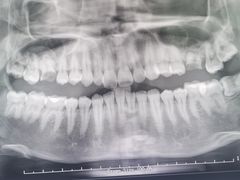

• 牙博士口腔品牌连锁(杨浦店)

• -牙博士口腔品牌连锁(杨浦店)